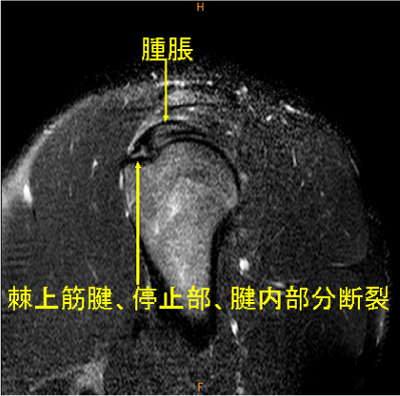

MRI所見

腱内の所見は脂肪抑制T2WIでないと描出するのが難しい。

AC jointの変化は慢性の変化で、棘上筋腱の所見がウエイトトレーニング時の外傷による変化であると想像される。

棘上筋腱停止部腱内の剥離, 腫脹著明, AC-jointのOA